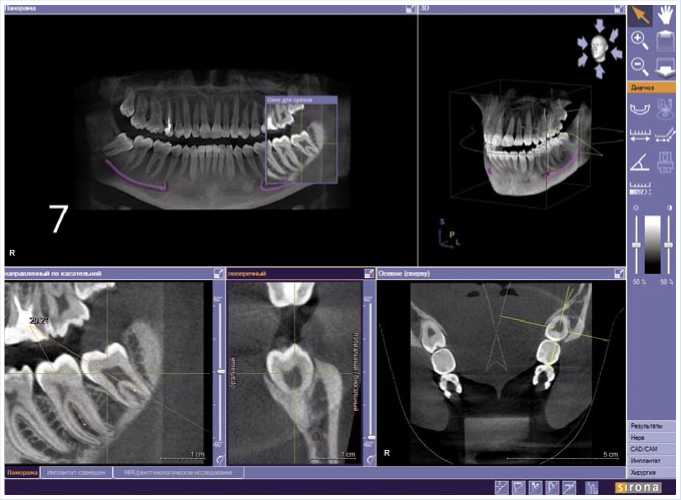

Далее Представлено трехлетнее наблюдение пациента с оценкой прогноза

Рис. 1. Пациент К., 16 лет. Срез компьютерной томограммы. Определяется зачаток зуба 3.8.

прорезывания нижних третьих моляров на основании результатов КЛКТ-иссле-дований по вышеуказанным парамен-трам.

Далее КЛКТ-исследования зубочелюстной системы пациента К. проводили в динамике: КТ-1 в возрасте 16 лет (Рис. 1), КТ-2 – в 18 лет (Рис. 2) и КТ-3 в возрасте 19 лет (Рис. 3) с интервалами 28 и 6 месяцев, соответственно. При сравнении значений КТ-1 и КТ-2 выявлена положительная динамика изменения положения зуба 3.8 (уменьшение угла между зубами 3.7 и 3.8), рост корней в длину. Динамика на КТ-2 и КТ-3 была незначительна, что дает основание считать интервал между КТ-исследованиями менее 6 месяцев малоинформативным. В итоге, по истечению 3 лет наблюдений имеем изменение положения зачатка зуба 3.8 и тенденцию к самостоятельному прорезыванию.